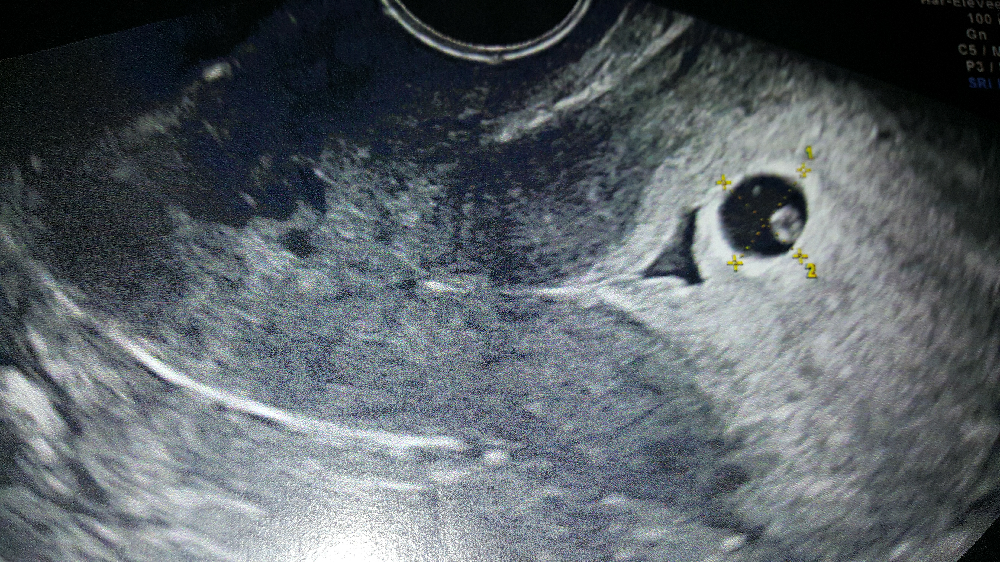

On 31207, showing a single intrauterine gestational sac of 8.4 mm... Download Scientific Diagram

Dans le cas d'une grossesse intra utérine d'évolution incertaine (sac gestationnel intra-utérin < 25 mm) sans vésicule vitelline visible, l'absence d'apparition d'un embryon avec une activité cardiaque à l'échographie endovaginale dans un délai d'au moins 14 jours permet d'affirmer que la grossesse est arrêtée (Grade C).

A ce moment, le diamètre moyen du sac est de 2 à 3 millimètres. À environ 5,5 semaines, le sac vitellin peut être vu à l'intérieur du sac gestationnel. Lorsqu'il est corrélé avec les niveaux d'hCG, un sac gestationnel doit être observé à l'échographie à environ 5 semaines lorsque le niveau d'hCG a atteint environ 1500 à.

Aspect echo graphiques au 1er mois. C'est vers quatre semaines et demie d'aménorrhée que l'on peut commencer à voir le sac gestationnel en échographie, à condition d'utiliser la voie vaginale. Au début, le sac gestationnel n'est qu'un tout petit point noir à l'intérieur de l'utérus. Il va progressivement augmenter de.

La visualisation d'une image de vésicule vitelline au sein d'un sac gestationnel permet donc d'affirmer le caractère intra-utérin de la grossesse. Mesure du sac gestationnel et grossesse arrêtée En 2011, une revue systématique (n = 872)(2) et une étude prospective multicentrique (n = 1 060)(3) ont bousculé les habitudes et.

L'aspect échographique du tout début de grossesse. Le premier signe échographique d'une grossesse est la visualisation d'un sac ovulaire. Il est visible entre 4 semaines et 1 jour et 4 semaines et 3 jours; Il mesure alors 2 à 3 mm.L'utilisation de la voie endovaginale est souvent nécessaire pour le voir.

On parle d'œuf clair lorsque l'œuf ne contient aucun embryon : le sac gestationnel est « clair ». Il ne contient ni embryon ni vésicule vitelline.Pour autant, on ne parlera de grossesse arrêtée que lorsque le sac gestationnel aura atteint 25 mm ou plus. S'il est de taille inférieure, il faudra recontrôler, car il est possible qu'il y ait eu erreur dans le calcul de la date de.